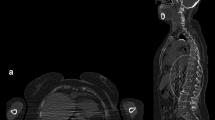

PET/CT acquisition

Patients should be imaged in the supine position with arms alongside the body. However, special caution must be taken to avoid CT truncation artefacts. If available, an extended field of view (FOV) for both the CT and PET components of the study is recommended; the PET coverage should not deviate from the FOV used for the CT component. The CT and PET acquisitions should be conducted from the skull vertex to the toes (or at least to the knees). Acquisition of the PET component should start from toes and proceed cranially to ensure that the bladder, which fills during imaging acquisition, is as empty as possible after pre-scan voiding; this reduces the risk of misalignment with the CT component due to an enlarged bladder and minimizes scatter and halo artifacts. For a standard step and shoot non-continuous bed motion PET/CT, the time of PET acquisition is approximately 2–3 min per bed position and can be adapted accordingly in continuous motion or large axial FOV PET systems.

For CT, protocols should follow national guidelines and be chosen regarding the objective of the examination according to the supervising board certified practitioner’s suggestion. Whereas whole-body low-dose CT (WB-LDCT) is considered the standard in MM, diagnostic contrast-enhanced scans can be performed in patients with normal kidney function and adequate hydration if applicable [14].

Image reconstruction